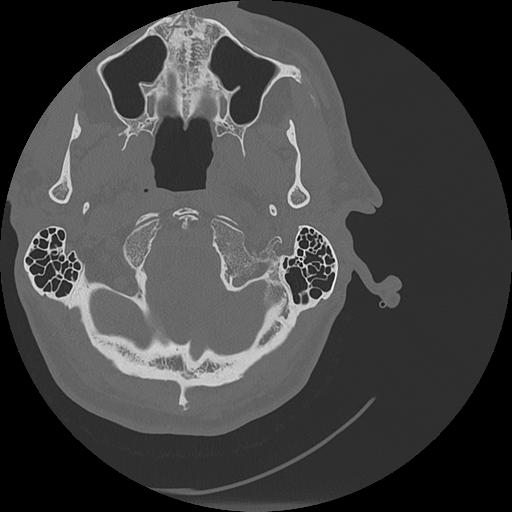

7 HUESO,,Vol,0.5,HUESO,,